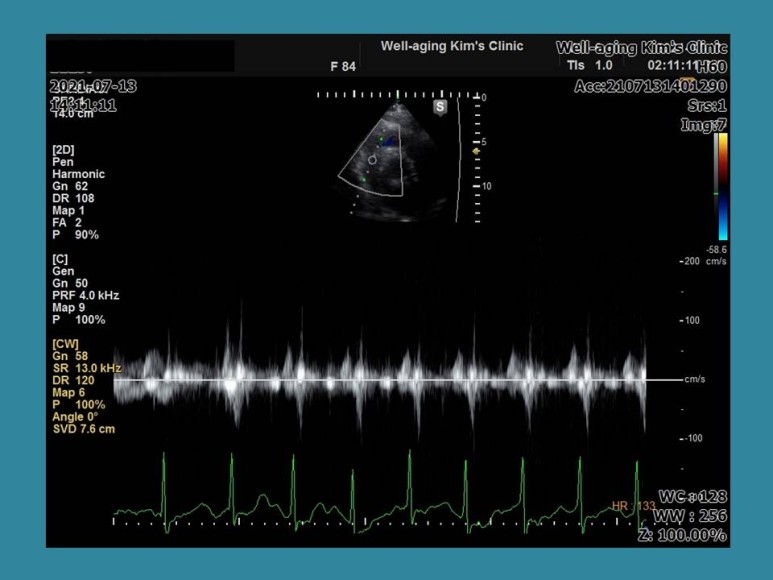

심장 초음파 검사를 실시하는 동일 안심 장박동수가 130회/분으로 갑자기 빨라지고 다시 정상 리듬으로 돌아왔다.가

이번에는 갑자기 심장박동기가 40~50회/분으로 느려지다가 중간에 동성정지 소견이 나타나고 불규칙한 맥박으로 바뀌는 상황이 3~4회 반복됐다.

이 경우 전형적인 빈맥-서맥증후군에 해당하며 환자가 증상은 없었지만 일단 수술을 중단하고 상급병원으로서 24시간 심전도 등의 검사가 필요하다는 것을 설명하고 이 환자는 인공심장박동기를 삽입할 수도 있는 경우이다.

이 환자의 경우도 외부 병원에서 찍은 심전도는 정상이었으나 심장 초음파 검사 중 우연히 부정맥이 발현돼 진단을 받은 경우다.